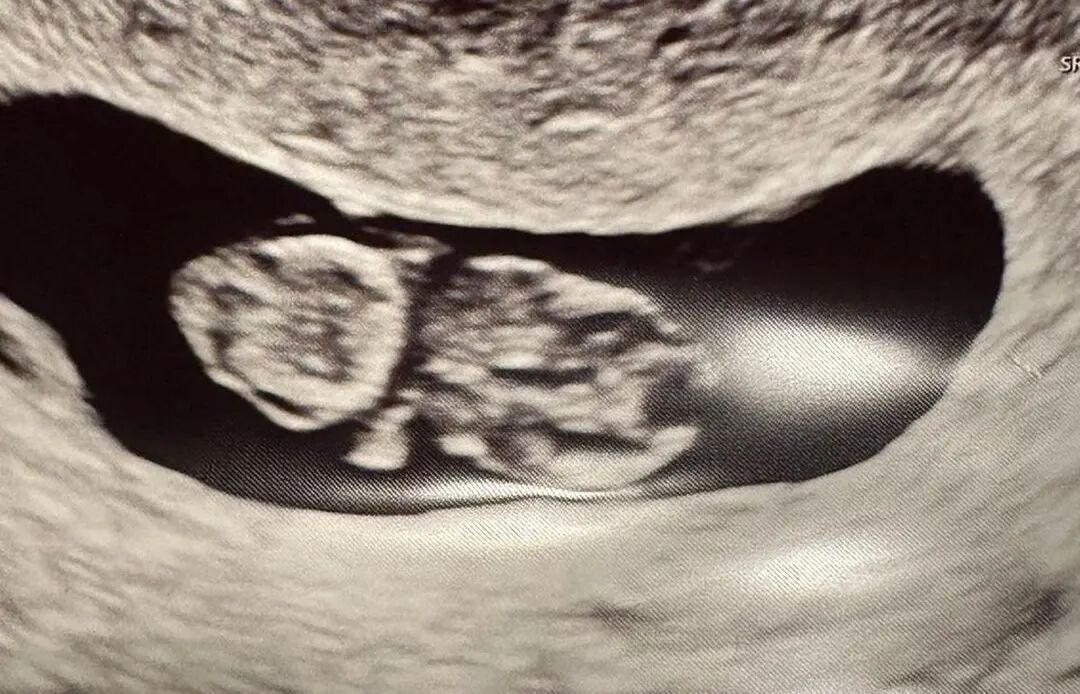

爱妈B的双胎宝宝健康成长中!宝宝们目前已有十周零六天大。我们准父母这次在捐卵女生的帮助下,成功培育出高品质的胚胎,两个宝宝均顺利着床。爱妈B将转至当地妇科诊所继续监控宝宝们的健康发展。